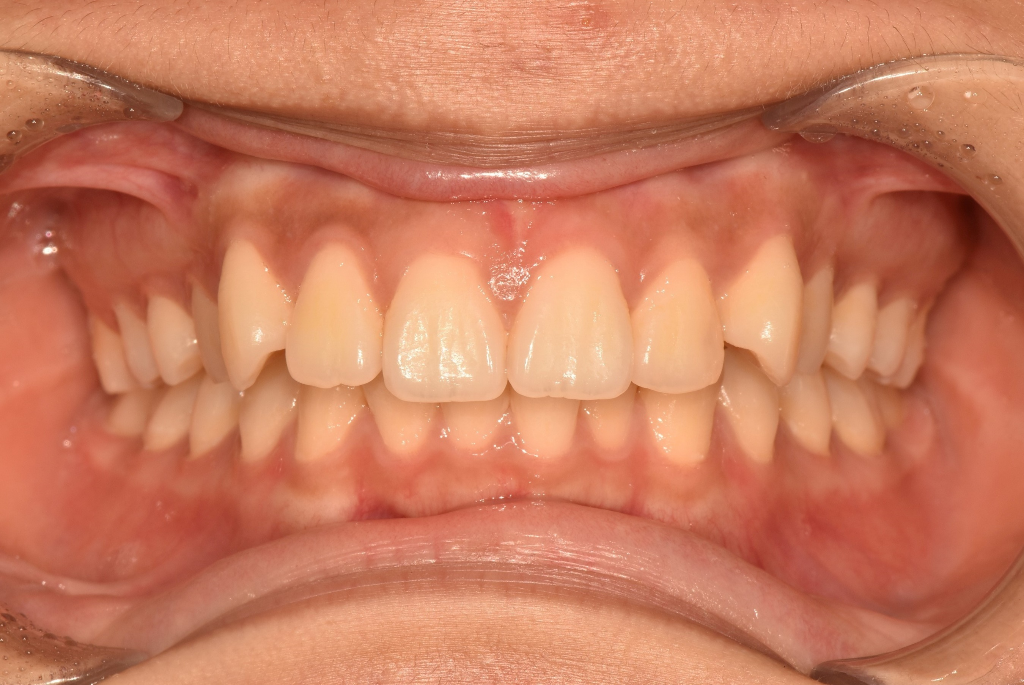

과개교합이라는데, 어느정도 일때부터 교정치료를 해야하나요?

아랫니가 틀어지기 시작해서 치과갔더니 과개교합이라고해요. 그동안 심미적, 기능적으로 불편함을 못 느꼈는데 과개교합을 방치하면 나이먹어 증상이 점점 심해져 치아건강에 안좋으니 윗니 발치하고 교정을 해야한대요.

이 정도 과개교합도 부작용, 불편함을 감수하고 교정을 해야하는지 궁금해요

3. 정상교합과 비교해봤을 때 과개교합(deep bite)이 지금 아주 심한 상태는 아닙니다. 다만 위 치아가 아래 치아에 비해 전방 위치하고 있는데 이건 원인이 턱(위턱)때문인지 아니면 단순히 치아가 경사져서 그런지는 방사선 사진을 찍어봐야 판단이 내려집니다.

4. 이렇게 윗니가 좀 튀어나온 경우 전체적인 안모(얼굴외형)에도 영향을 주고 있을 수 있습니다. 입술과 인중 부위가 과긴장 상태로 약간 불룩하게 튀어나와 보일 수 있겠습니다. 말씀주신 것처럼 발치교정이 필요할 수도 있겠습니다.